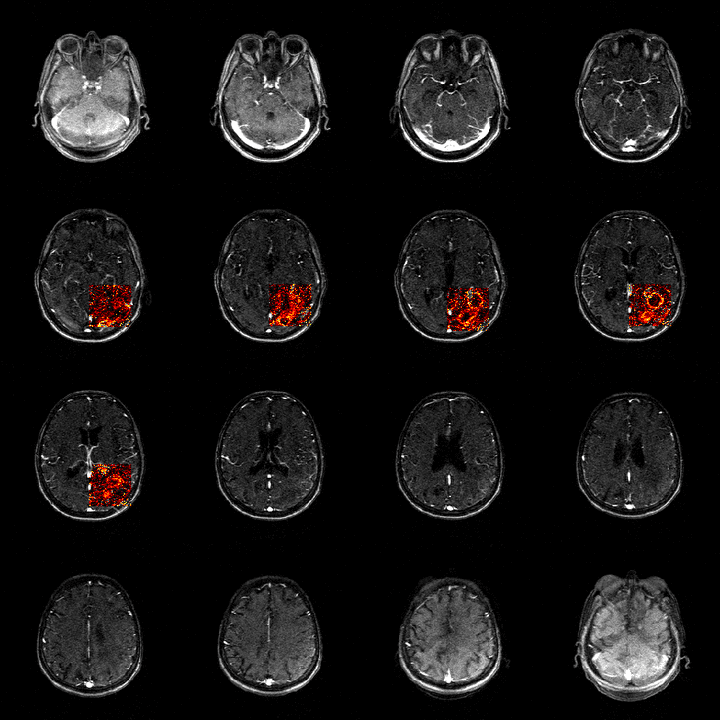

Estimated Ktrans values for a subject in the RIDER Neuro MRI collection from The Cancer Imaging Archive (TCIA)

• dcemriS4: R package for the quantitative analysis of dynamic contrast-enhanced MRI (DCE-MRI) and diffusion-weighted imaging (DWI) for oncology applications. It provides methods for fitting voxel-wise kinetic models using Levenberg-Marquardt and using a Bayesian framework. Several kinetic models and arterial input functions are available.